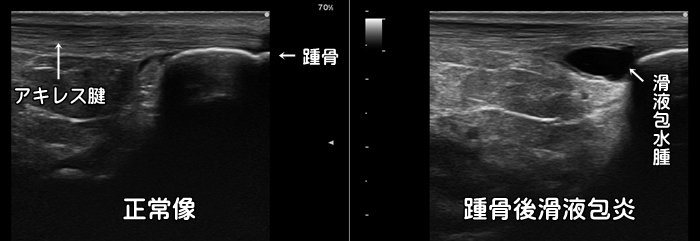

踵骨後滑液包炎

アキレス腱と踵の骨の間には滑液包と呼ばれるクッションが存在します。この滑液包がランニングなどの激しい運動による摩擦で炎症を起こすと中に水が溜まり無エコー(黒)に描出されます。長引くアキレス腱周囲の痛みの原因になります。